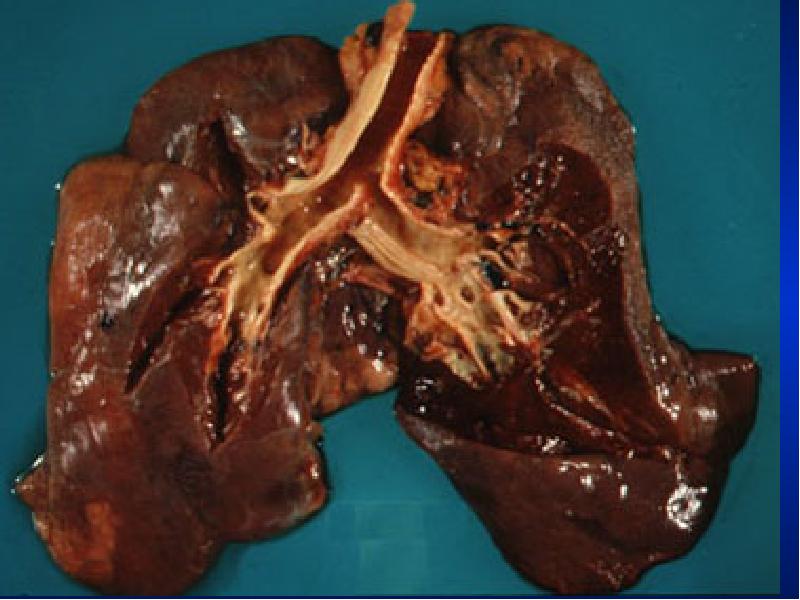

- 5. Illustrative Pathological problems Consolidation Atelectasis Pleural effusion Pneumothorax Mass Diffuse lung